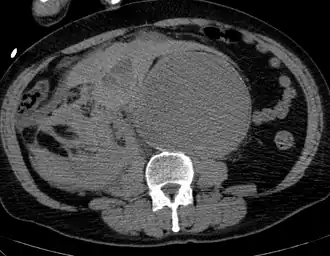

The diagnosis of an abdominal aortic aneurysm can be confirmed by the use of ultrasound. Rupture may be indicated by the presence of free fluid in the abdomen. A contrast-enhanced abdominal CT scan is the best test to diagnose an AAA and guide treatment options.[10]

Diagnosis

In terms of the diagnosis the medical practitioner will feel your abdominal area, listen for a heart murmur, and check symptoms of conditions that are risk factors for aortic aneurysm( Marfan or Ehlers-Danlos syndromes).They may also run an image:[14]

- MRI

- Ultrasound